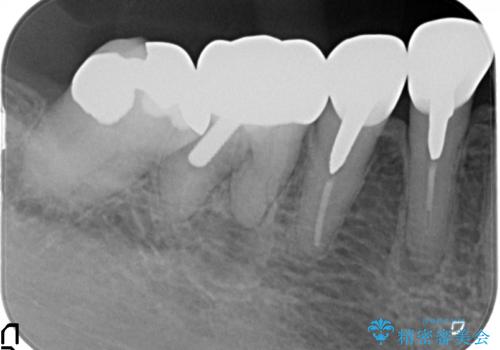

大臼歯 再根管治療

- 銀歯を白くしたいとの希望で来院されました。

せっかく銀歯を白くしても後々根管治療が必要になり、また壊して再治療を行うことを避けたいとの事でしたので、再根管治療から行っていきます。

ただ銀歯を白くするのではなく長期的な予後には歯の内部、根管治療の成功が必要不可欠です。